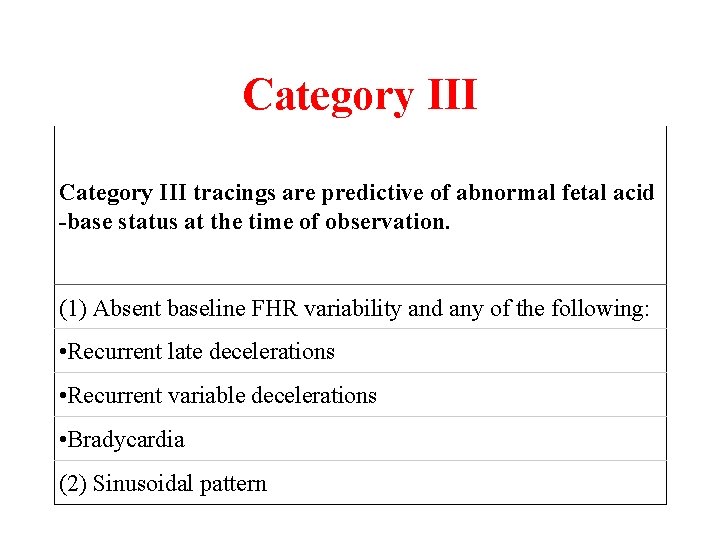

Category III tracings are predictive of abnormal fetal acid -base status at the time of observation. (1) Absent baseline FHR variability and any of the following: • Recurrent late decelerations • Recurrent variable decelerations • Bradycardia (2) Sinusoidal pattern